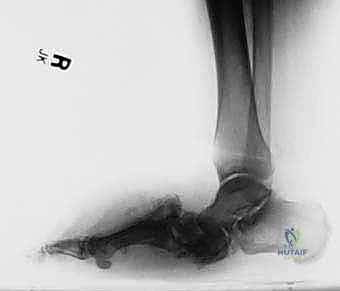

عندما تتضافر هاتان النظريتان، ينهار قوس القدم تماماً، وتبرز العظام نحو الأسفل، مما يخلق ما يُعرف بـ "قدم الكرسي الهزاز" أو "قدم الروكر" (Rocker-bottom Foot)، حيث يصبح باطن القدم محدباً بدلاً من أن يكون مقعراً. هذا البروز العظمي يضغط بشدة على الجلد من الداخل، مما يؤدي سريعاً إلى تقرحات عميقة، التهابات بكتيرية، وتسمم الدم، وهو ما ينتهي غالباً بالبتر إذا لم يتم التدخل الجراحي المتخصص في الوقت المناسب.

- المرحلة الأولى (مرحلة التطور والتفتت): تدمير حاد. تظهر الأشعة تفتت العظام، خلع المفاصل، وتكون شظايا عظمية. القدم تكون حمراء، ساخنة، ومتورمة بشدة.

- المرحلة الثالثة (مرحلة التصلب وإعادة البناء): تبرد القدم وتستقر، لكنها تلتئم على وضع مشوه بشدة (قدم الروكر)، مما يمهد الطريق للتقرحات المستعصية.